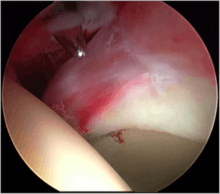

Labral tears

The acetabular labrum is a fibrous structure, which surrounds the femoral head. It forms a seal to the hip joint,[15] although its true function is poorly understood. Recent evidence has demonstrated that this hydraulic seal is vital for maintaining stability of the ball and socket joint [16] and reducing contact pressures of the femur to the acetabulum.[17] The labrum has also been shown to have a nerve supply and as such may cause pain if damaged.[18] The underside of the labrum is continuous with the acetabular articular cartilage so any compressive forces that affect the labrum may also cause articular cartilage damage, particularly at the junction between the two, the chondrolabral junction. The labrum may be damaged or torn as part of an underlying process, such as FAI or dysplasia (shallow hip socket), or may be injured directly by a traumatic event. Depending on the type of tear, the labrum may be either trimmed (debrided) or repaired. Removing or debriding the labrum is becoming less popular as the latest research shows that results are more predictable in the long term if the labrum can be repaired. Various techniques are available for labral repair, mainly using anchors, which may be used to re-stabilise the labrum against the underlying bone, allowing it to heal in position.

New techniques are prevalent in hip arthroscopy. There is good evidence to support the creation of a new labrum (labral reconstruction) if the patient has previously had a labral debridement, has an ossified labrum, or the current labrum is too small or injured for a repair.[16] Labral reconstruction involves creating a new labrum either from the patients own tissue (autograft) or from cadaver tissue (allograft). The new labrum is then anchored into position with bone anchors and the hip then goes through extensive rehab.